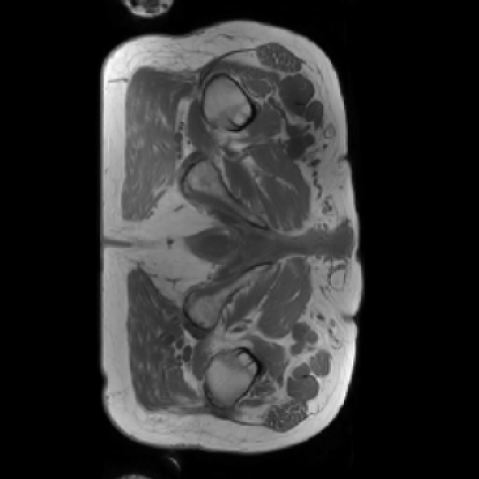

The motivation for this work arises from the need to address these limitations in the synthesis of 3D medical images. Current techniques do not produce high-resolution 3D images that preserve spatial coherence and capture the full complexity of medical data, as shown in Figure 2, 5. The development of advanced 3D generative models tailored specifically for medical imaging could not only improve the quality of synthetic medical images but also help alleviate data scarcity, enhance privacy protection, reduce computational requirement and ultimately advance the use of deep learning in healthcare applications.

As shown in Figure 5, the generated slices exhibit high consistency across adjacent slices. The anatomical structures and semantic patterns are smoothly and coherently preserved between slices, indicating that our model is capable of generating 3D-consistent synthetic images rather than isolated 2D slices.

Figure 8 further supports these findings: the images generated by Med-LSDM preserve spatial coherence across coronal and sagittal planes, whereas those from SegGuidedDiff show noticeable inconsistencies. These artifacts likely result from the 2D nature of SegGuidedDiff, which fails to account for 3D spatial relationships. In contrast, our model’s volumetric diffusion framework inherently preserves anatomical consistency, highlighting its advanta in synthesizing high-fidelity 3D medical images.